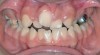

A common developmental abnormality is a localized anterior crossbite on permanent incisors, which may lead to trauma to these teeth. The most common cause of localized incisor crossbite is an anterior occlusal interference, which causes a functional shift when the patient moves from centric relation to centric occlusion (Figure 1 and Figure 2). This is not a true class III malocclusion, and proper diagnosis is critical to select the correct treatment. Sometimes this bite relationship is called a pseudo-class III relationship.2 Intervention in these cases is important because these teeth are at higher risk for recession, periodontal damage, and incisal chipping. Limited anterior braces and sometimes a palatal expander may be used to place the maxillary incisors facial to the mandibular incisors; this is referred to as "jumping the bite."

Fig 1. Functional shift in centric occlusion.

Figure 1

Fig 2. Functional shift in centric relation.

Figure 2